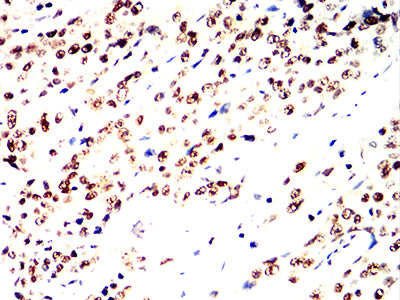

- Immunohistochemical analysis of paraffin-embedded human liver tissues using RFA2 mouse mAb with DAB staining.